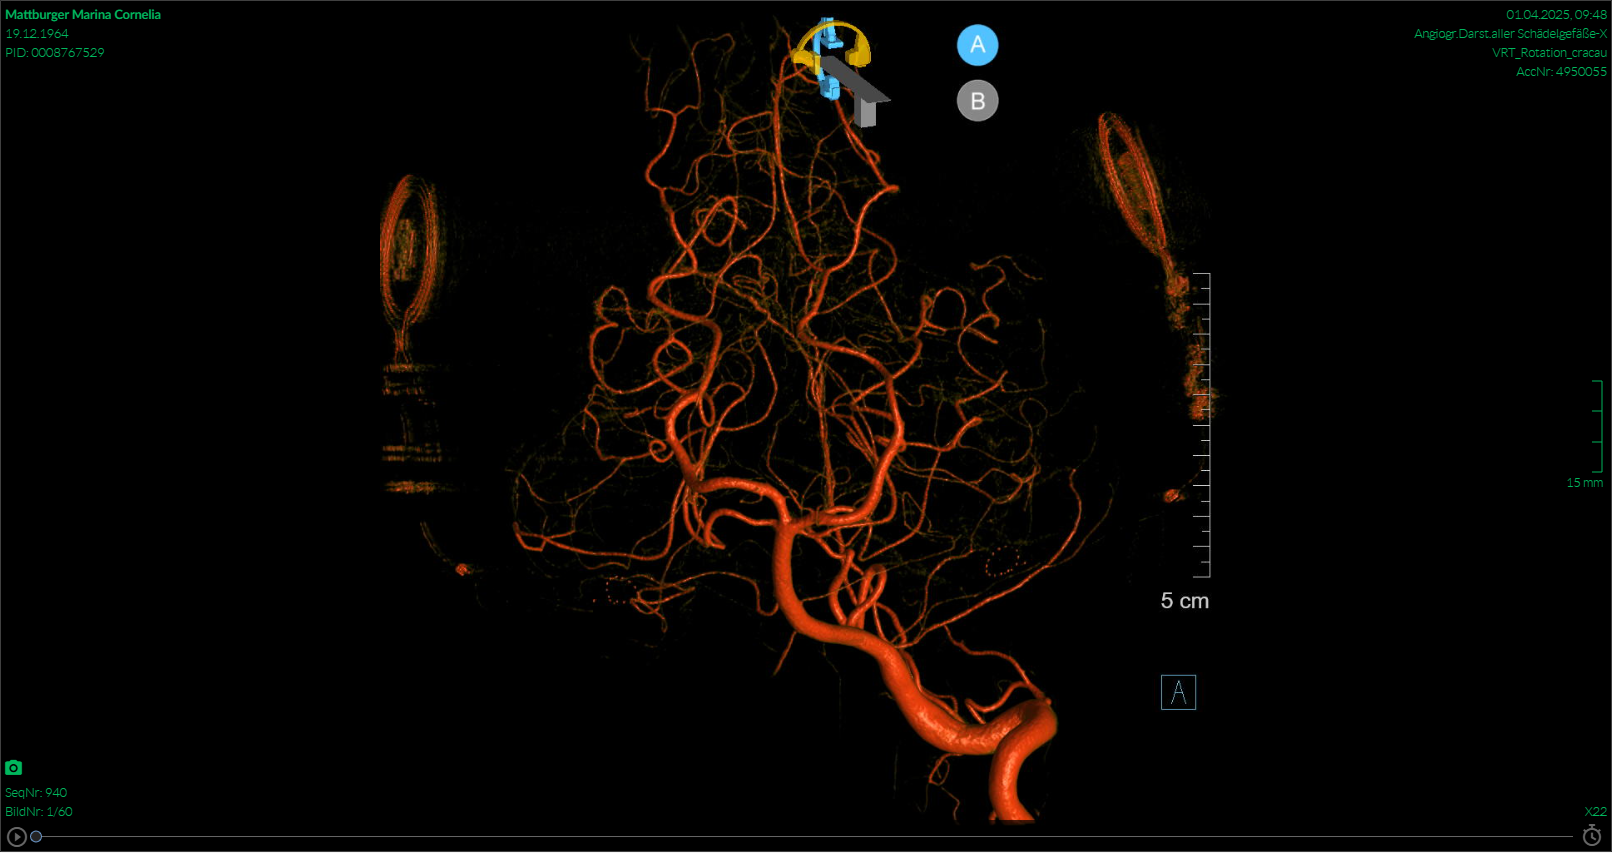

Die Blutabnahme auf der Intensivstation hat auch nicht viel an den Tag gebracht. Daher entschied man sich, eine Untersuchung der Blutgefäße im Kopf zu machen. Eine digitale Subtraktionsangiographie-Untersuchung (kurz DSA genannt) zeigte wahnsinnig tolle Bilder, aber auch bei dieser Untersuchung kam zum Glück nichts raus.

Es ist eine Untersuchung, die mit einem Katheter in der Armvene und ständiger Gabe von Kontrastmittel stattfindet. Für den behandelnden Arzt war es auch was ganz Neues, jemanden Gehörloses hatte er noch nie auf der Liege. Aber da er mir, so lange ich das CI noch tragen konnte, alles bestens erklärt hat, wusste ich Bescheid und habe mich keinen Millimeter bewegt, die ganze Sache auf dem großen Bildschirm etwas beobachten können und im richtigen Moment genau das getan, was er mir gesagt hatte.

Luft anhalten und erst wenn das Kontrastmittel dort ankommt, wo es sein soll (das merkt man sehr deutlich) wieder weiteratmen. Also, ich habe wohl alles richtig gemacht.

Es geht mir wieder gut, das ist die Hauptsache. Die Bilder zeigen Aufnahmen vom MRT und von der Subtraktionsangiographie. Ich hoffe, ich mache euch ein wenig Mut, keine Angst vor solchen Untersuchungen zu haben. Auch mit CI geht das!